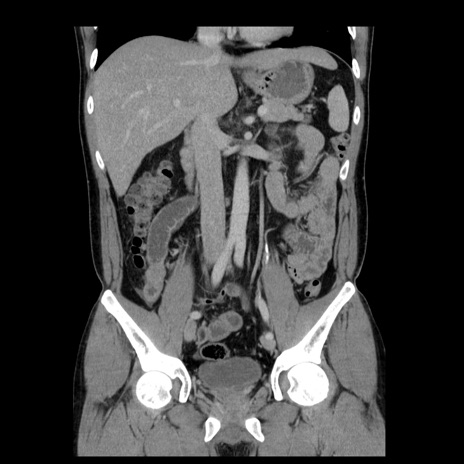

症例4(冠状断像)

【症例】30歳代男性

【主訴】腹痛、嘔吐

【現病歴】昨晩から突然の腹痛あり、その後嘔吐、軟便も出現。腹痛が改善しないため救急搬送となる。2日前にしめ鯖の食事歴あり。

【身体所見】意識清明、苦悶様、BP 135/90mmHg、BT 35.7℃、腹部:平坦、やや硬、心窩部〜臍部に自発痛、圧痛あり、筋性防御+、反跳痛-

【データ】WBC 8100、CRP 0.57